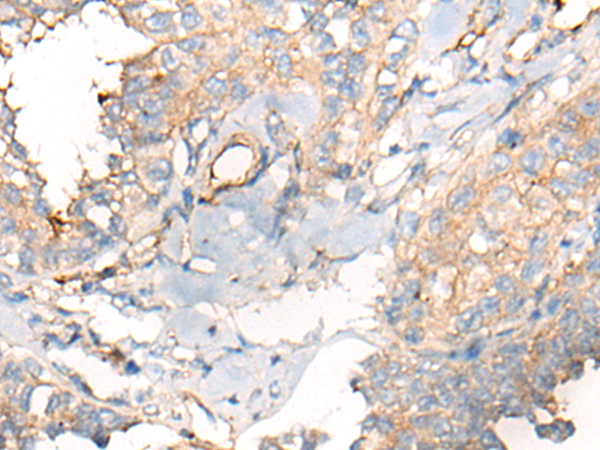

IHC positive control: |

Human lung cancer and human ovarian cancer |

IHC Recommend dilution: |

10-50 |